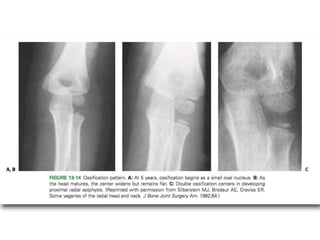

• In the embryo, the proximal radius is well defined by 9 weeks of gestation.

• By 4 years of age, the radial head and neck have the same contours as in an

adult.

• Ossification of the proximal radius epiphysis begins at approximately 5 years of

age as a small, flat nucleus.

• This ossific nucleus can originate as a small sphere or it can be bipartite, which

is a normal variation and should not be misinterpreted as a fracture.